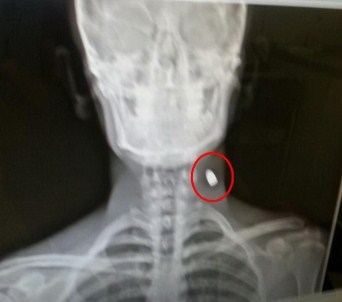

Yaşadığı şok verici durumu anlatan lise son sınıf öğrencisi Onur Yüksel, “Kurban Bayramı’nın 3. günü akşamı evin avlusunda bir anda başıma darbe hissettim. Uzun süre kanama oldu. Çizik gibi bir iz vardı. O gece hastaneye gittik. Hastanede doktorlar baktılar ama hiçbir şeyin olmadığını söyleyerek geri gönderdiler. Biz de bir şey yok denilince telaşlanmadık. Herhangi bir durumun olabileceğini düşünmedik. Belli bir zaman sonra Samsun’da bir AVM’ye alışveriş için gittik. Orada içeriye girerken X-Ray cihazı öttü. Güvenlik görevlileri beni içeri almadı. Şüpheli biri olduğumu düşünerek üzerimde arama yaptılar. X-Ray cihazını üzerimde gezdirince boynumda metal olduğunu söylediler. Özel bir hastaneye gittim. Burada röntgen çekildi. Çekilen röntgenle birlikte gerçek ortaya çıktı. Boynumda mermi çekirdeği olduğu anlaşıldı. X-Ray cihazında ki yaşadığım sıkıntıyla bu gerçeğin ortaya çıkması komik oldu” dedi.

9 ay boyunca boynunda mermi çekirdeği ile gezdiğini, herhangi bir ağrı hissetmediğini söyleyen Yüksel, Samsun Ondokuz Mayıs Üniversitesi Tıp Fakültesi Hastanesi’nde yarın ameliyat olacağını belirtti.